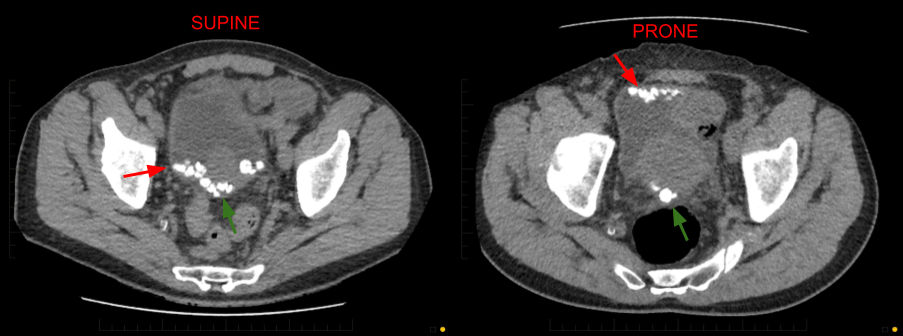

Ct Kub Supine Vs Prone

Percist Measurements From Prone And Supine Fdg Pet Ct Of The